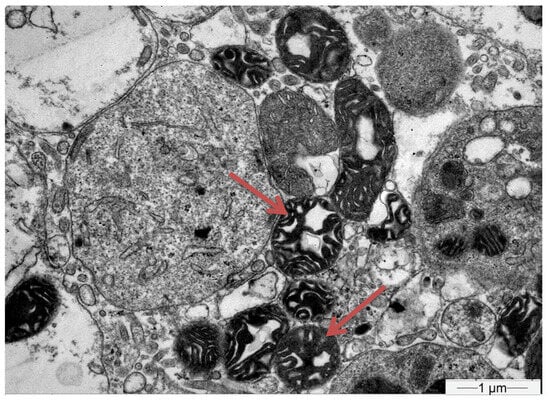

- Herlitz, L.C.; Mohan, S.; Stokes, M.B.; Radhakrishnan, J.; D’Agati, V.D.; Markowitz, G.S. Tenofovir nephrotoxicity: Acute tubular necrosis with distinctive clinical, pathological, and mitochondrial abnormalities. Kidney Int. 2010, 78, 1171–1177. [Google Scholar] [CrossRef] [PubMed]

| Biopsy | Proximal Tubular Injury | Not performed | Not performed | Not performed | Proximal Tubular Injury |